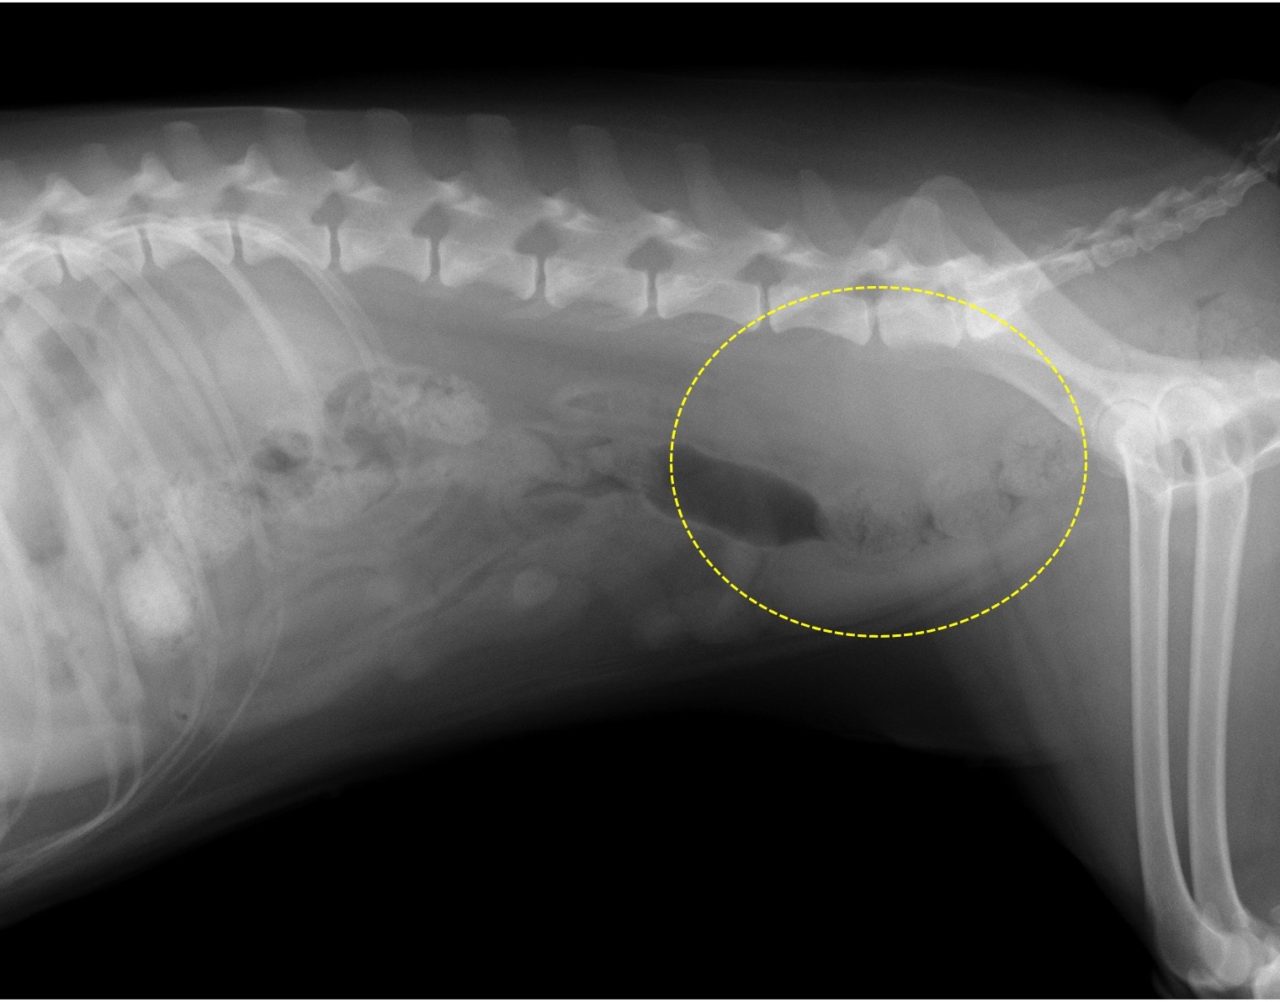

・レントゲン検査:リンパ節転移、遠隔転移の評価

肛門嚢腺癌のリンパ節転移(レントゲン画像)